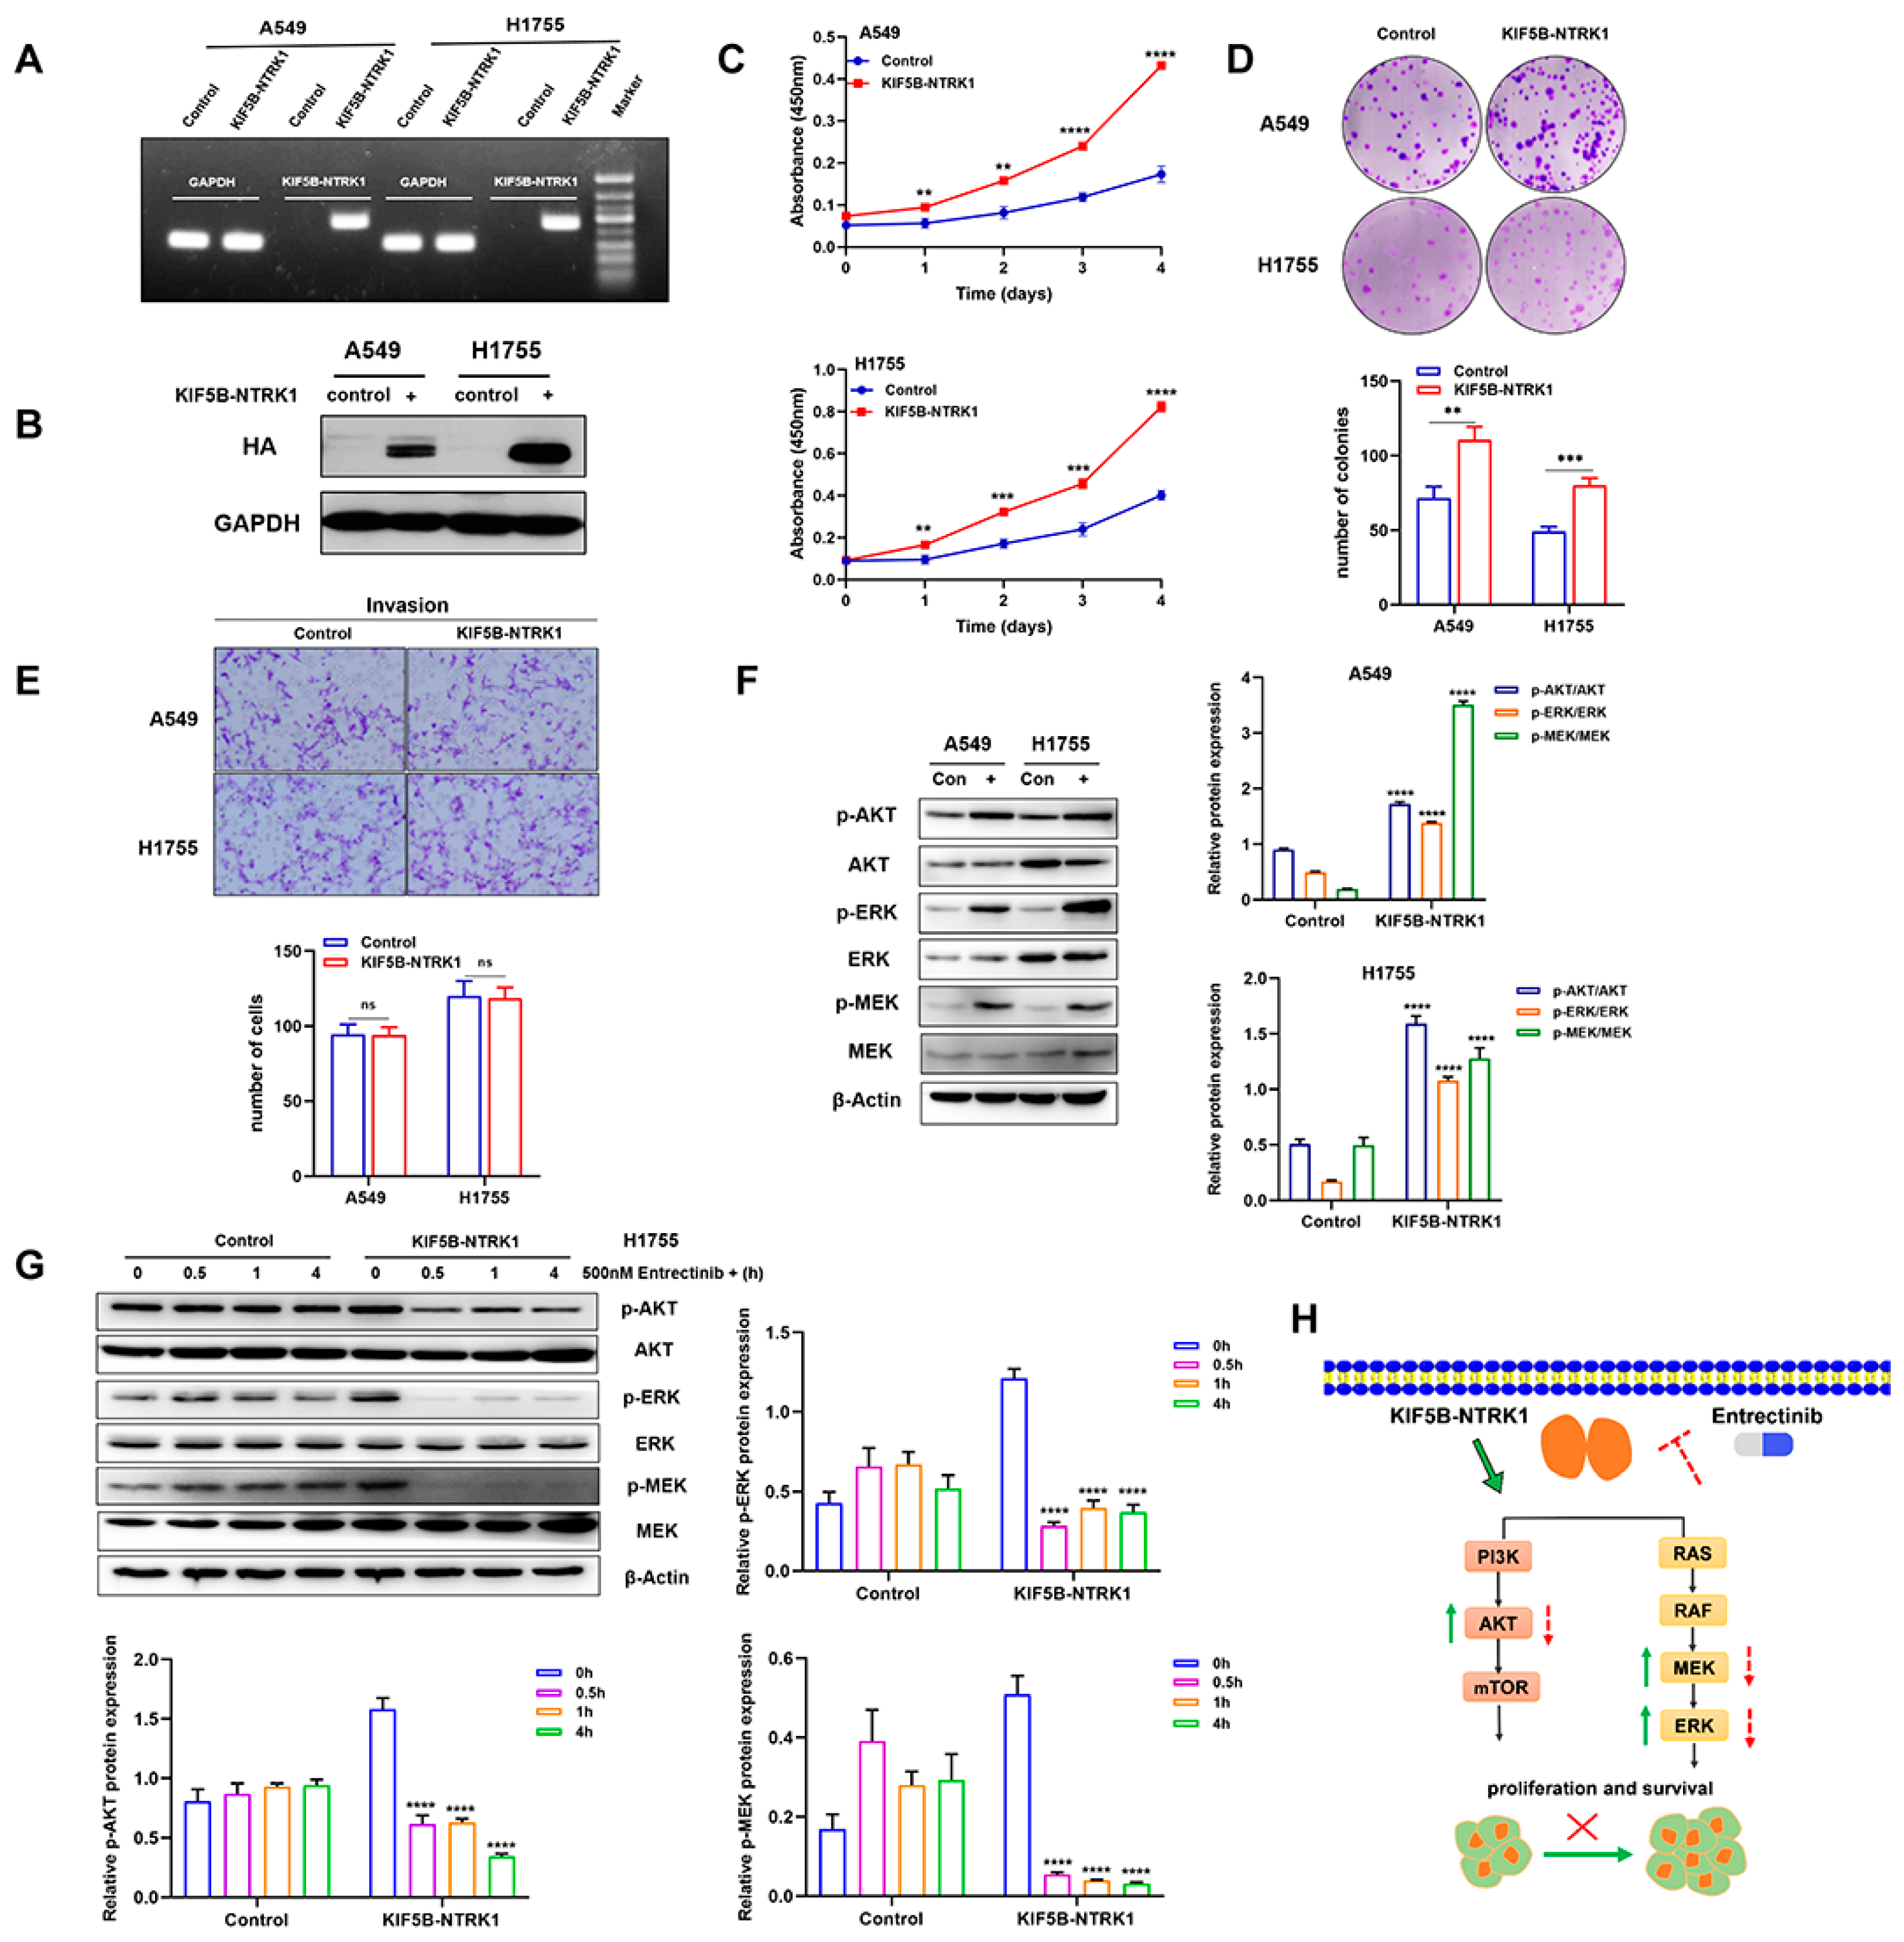

3.2. KIF5B-NTRK1 Promotes Proliferation and Adhesion-Dependent Colony Formation but Not Invasion

3.3. KIF5B-NTRK1 Activates the MAPK and PI3K-AKT Signaling Pathways